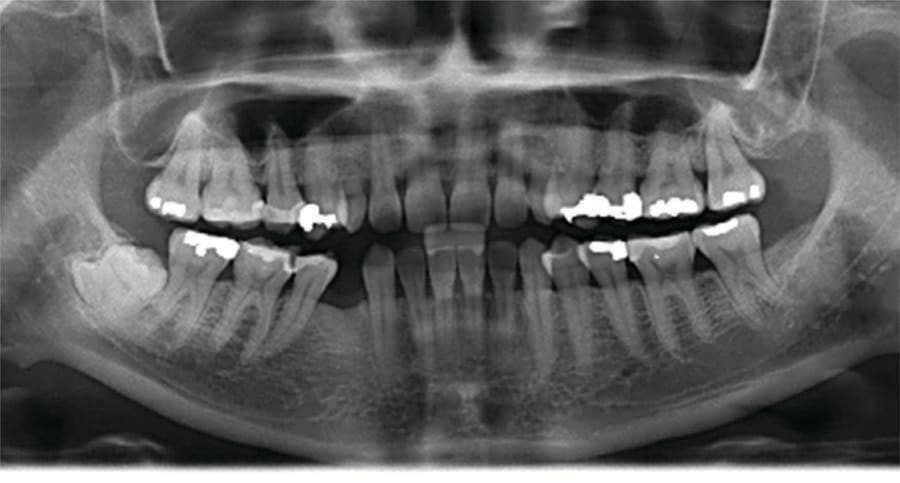

A 31-year-old Asian female presented for a consult. Her medical history was reviewed, and no health issues were noted. She indicated her last dental visit was 2 years ago and her chief complaint was that her deciduous canines felt loose and she was unhappy with her smile (Figure 1). Examination noted fair oral hygiene with light generalized calculus and moderate bleeding in the posterior with 4 mm probing on the molars. The deciduous canines were present bilaterally in the maxilla which were grade 1+ mobile (Figure 2). Cervical caries was noted on both deciduous teeth on the facial and also the distal of the left deciduous canine (Figure 3). Tooth No. 28 (right mandibular first premolar) was noted to be missing. The patient indicated the missing bicuspid never developed and the deciduous molar was lost in her teens. Physical examination noted a concavity in the vestibule apical to the gingival margin at both canine sites. A panoramic and bitewing radiographs were taken to evaluate the dentition and arches (Figure 4). Radiographically it was confirmed that the permanent maxillary canines were not present nor was the mandibular bicuspid. Further, significant resorption of the roots of the deciduous canines was noted.

Discussion was conducted with the patient on the treatment recommended to correct the problems noted and to achieve her expressed esthetic concerns to improve her smile. Recommended treatment included clear aligner orthodontics for both the maxillary and mandibular arch to create appropriate space to restore implants at the canine sites to blend with the adjacent teeth to achieve a natural smile. Additionally, restorations were recommended on the right mandibular second premolar (No. 29) and first molar (No. 30). The patient presented for a CBCT scan and a consultation with the oral surgeon, to evaluate the sites for bone block grafting. She was informed grafting was possibly indicated at the canine sites to create a site that could accommodate implant placement and encase the implants within bone. The patent indicated she was receptive to the recommended treatment. The patient was scheduled for the two recommended restorations on the two mandibular teeth and referred to the orthodontist for evaluation and treatment.